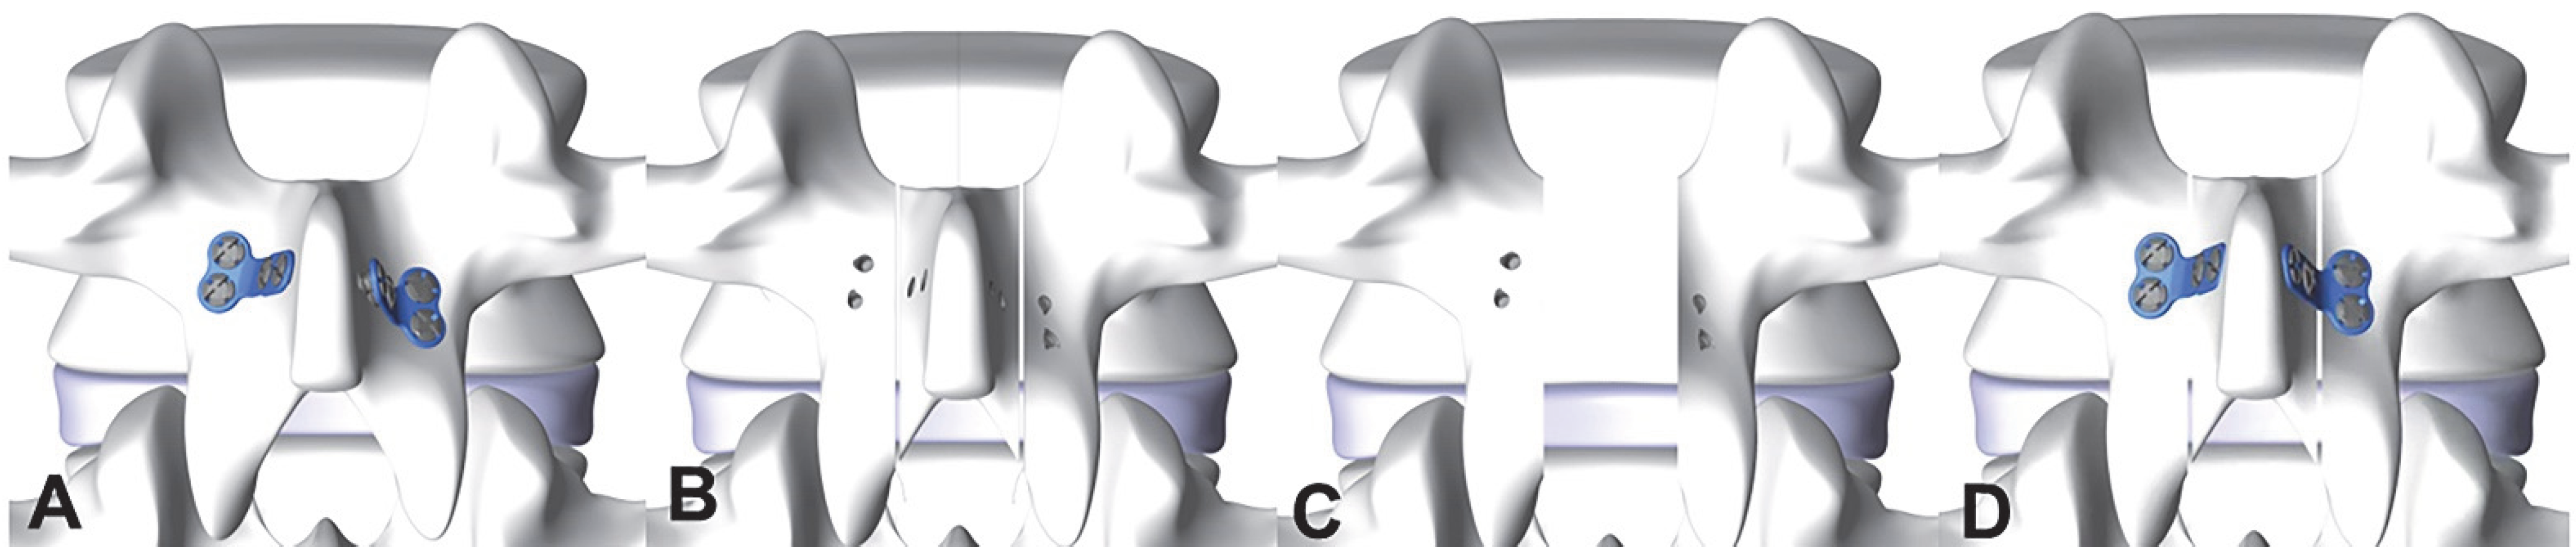

3.5. Results of the Biomechanical Experiments